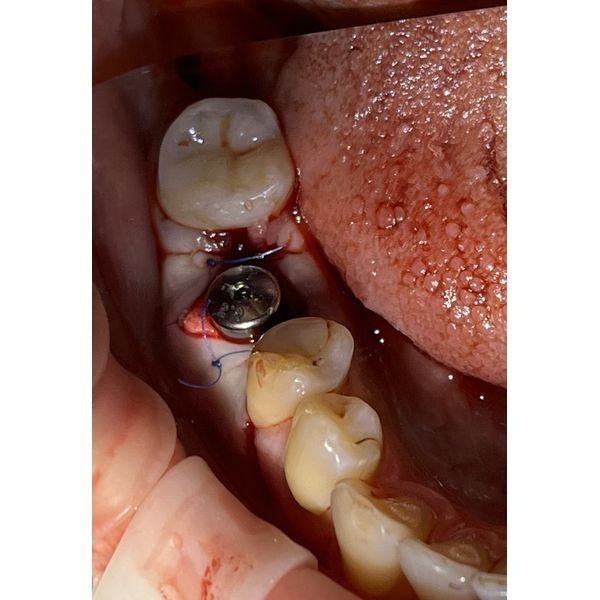

- установили имплант конической формы с торком (силой) 50 нсм: диаметр — 4,5, длина — 12 мм;

- установили формирователь десны, чтобы сократить период реабилитации и исключить повторное вмешательство перед ортопедическим лечением;

- ушили лунку П-образными швами (Пролен 5/0);

- проконтролировали, что кровотечение остановлено, и обработали рот раствором Хлоргексидина биглюконата.

На вторые сутки после операции сохранялся незначительный отёк слизистой оболочки в проекции лунки зуба 4.6 и ноющая боль. Швы состоятельные. Признаков острого воспаления и кровотечения не было.